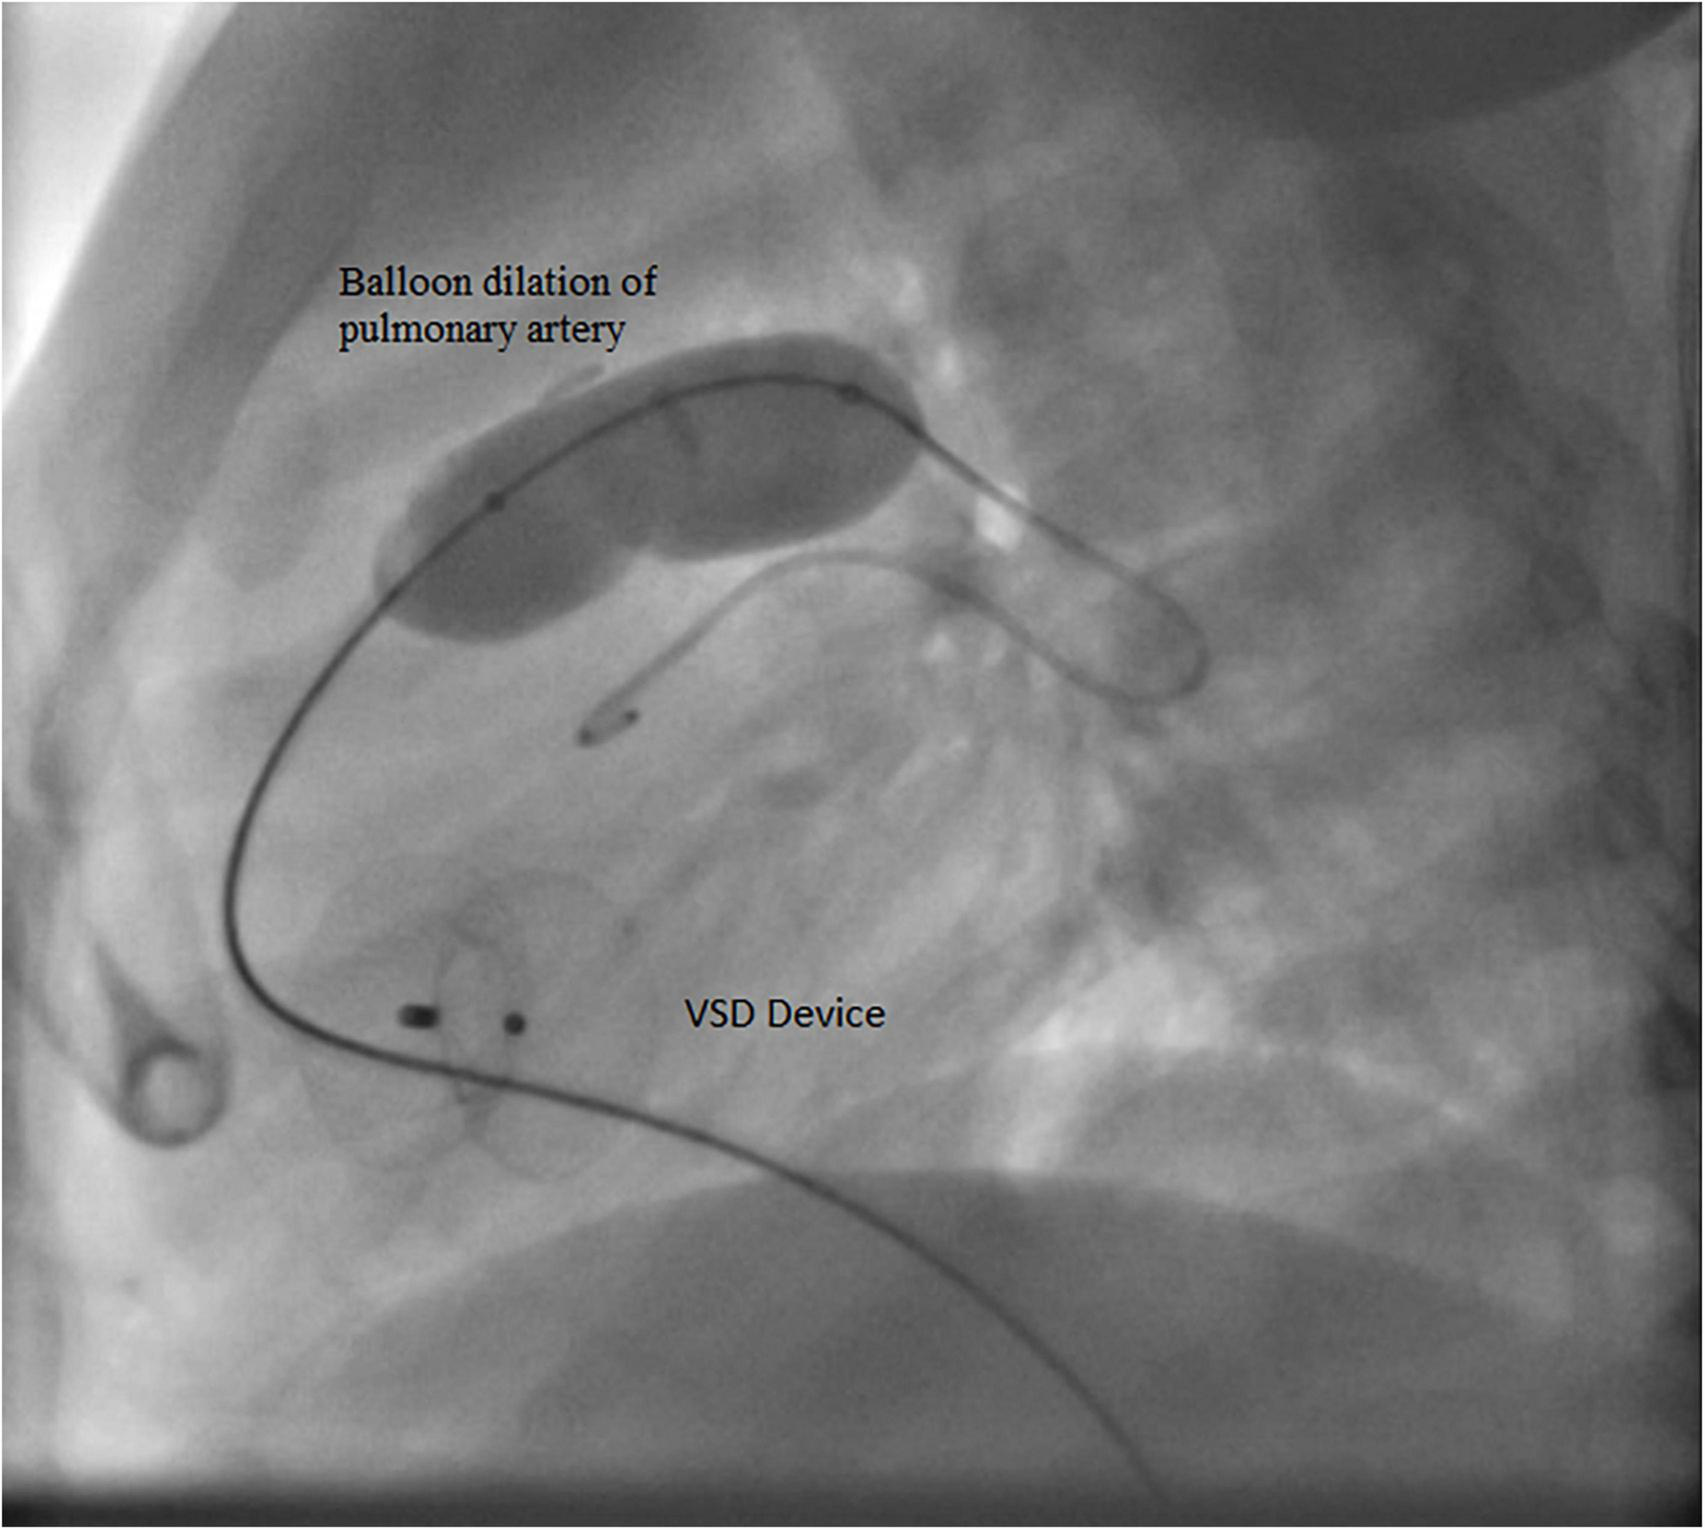

Case I: The first case of balloon dilation is a female patient who was diagnosed at birth with a large smooth muscular VSD measuring 13.5 mm in diameter and 7 mm in length. She had a PAB placed at the age of 2 months due to pulmonary overflow. At the age of 33 months, she presented for device VSD closure. Successful closure using a 16 mm amplatzer device was performed under general anesthesia without complications. Following the procedure, the right ventricular (RV) systolic pressure was measured at 85 mmHg, left ventricular (LV) systolic pressure was 95 mmHg, and the pressure gradient across the PA band was 60 mmHg. Three days later, balloon-based removal of the PA band was successfully performed under sedation, using 14 mm balloon (Figure 3). Pressure measurement following the procedure revealed: RV systolic pressure of 48 mmHg, and PA systolic pressure of 26 mmHg with a residual gradient of 22 mmHg across the band site. The patient tolerated the procedure well without complications and was pain-free by the second day following the operation, according to the Face, Legs, Activity, Cry, Consolability (FLACC) scale. She was followed up annually and when needed at the pediatric cardiology outpatient department via clinical and echocardiographic evaluation for 3 years following the percutaneous band removal; thereafter she was lost to follow up. At the last clinic visit, the patient was gaining weight adequately (weight = 20 Kg) and her systemic oxygen saturation was 100%. Her last echocardiographic imaging, at 3 years post-debanding, showed normal LV size and function, normal size of the main pulmonary artery, and an estimated RV systolic pressure of around 36 mm Hg. The patient was not maintained on any cardiac medications. Figure 4 shows the echocardiographic findings of the patient before the debanding procedure and at 3-year follow-up post debanding.

FIGURE 3

Balloon dilation of the pulmonary artery of Case I.